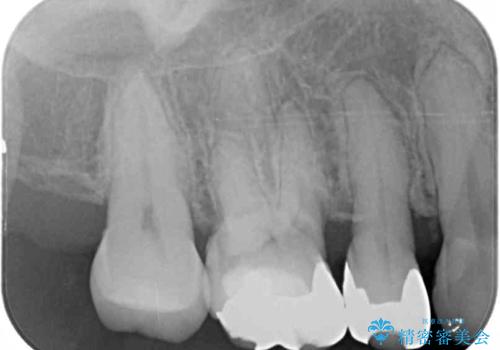

- 奥歯の裏側がしみるとのことで来院された患者様です。

矯正治療による歯肉退縮がおき、歯根にまで虫歯が波及していました。

虫歯が大きかったため、フルジルコニアクラウンにて補綴することとしました。